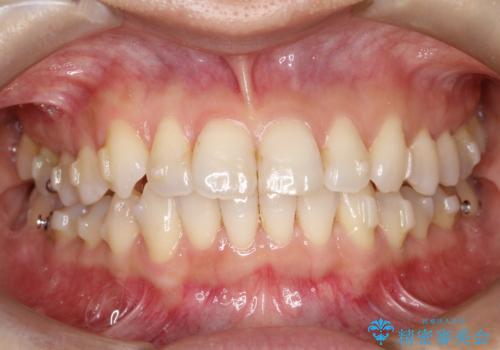

八重歯と前歯のガタガタをインビザラインで

- 八重歯と前歯のガタガタを主訴に来院されました。

目立たず矯正したいとのことでインビザラインで矯正することとしました。

インビザラインで目立たずに治療を終えることができ、喜んでいただけました。